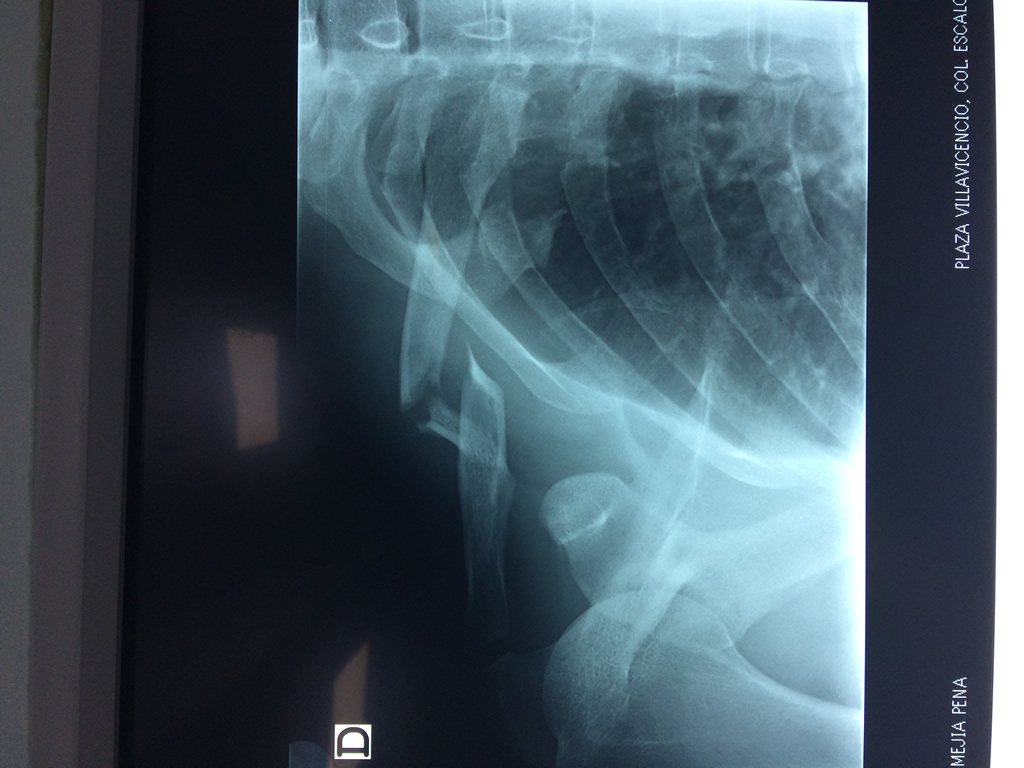

Cirugías de Calcaneo - Clavícula